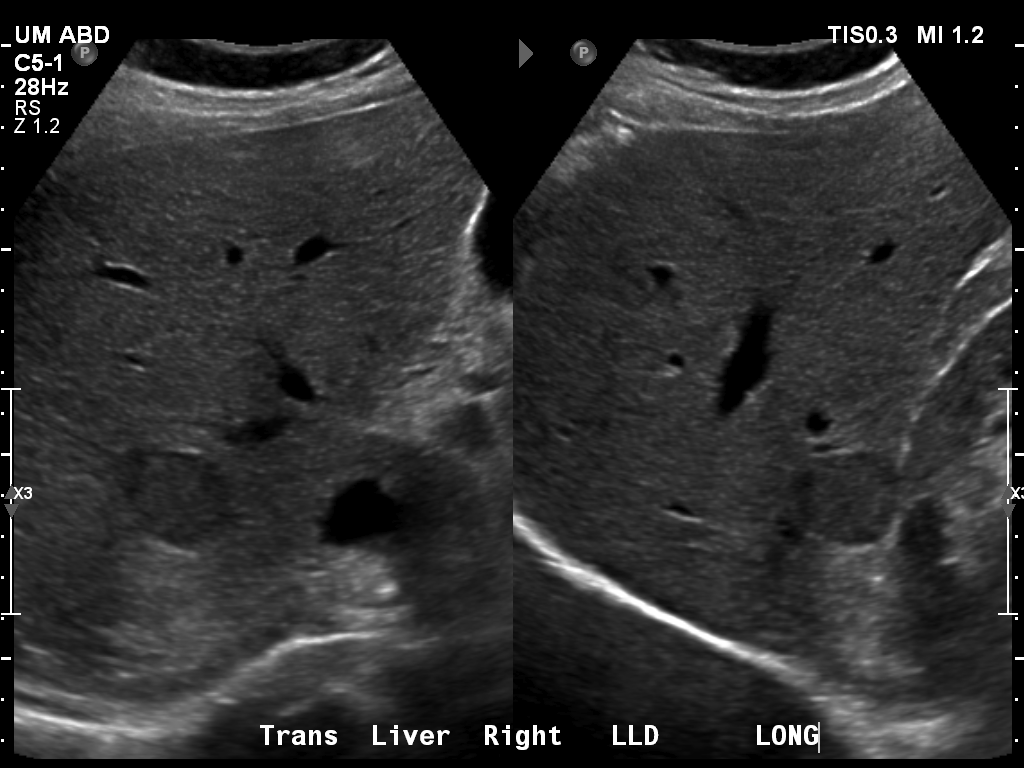

69 M with PMH of HCV cirrhosis & HCC s/p resection in 14 years ago presenting today for a screening ultrasound.

135/73 mmHg / 78 bpm / 16 breaths/min / 96.4°F

sclerae anicteric, no jaundice

CMP wnl, AFP 5